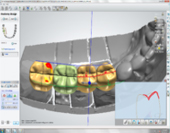

After thorough evaluation and diagnosis, which included Cone Beam CT scan, Digital Smile Design – DSD, 3D- intraoral Scanning etc, the treatment plan had been formulated.

Dr. Andrews is one of the most advanced CAD/CAM dentists in the world. He uses advanced intraoral digital 3D scanning technology with 10-micron precision (0.0004 inch) which produces a perfect replica for tooth restoration and implant placements…